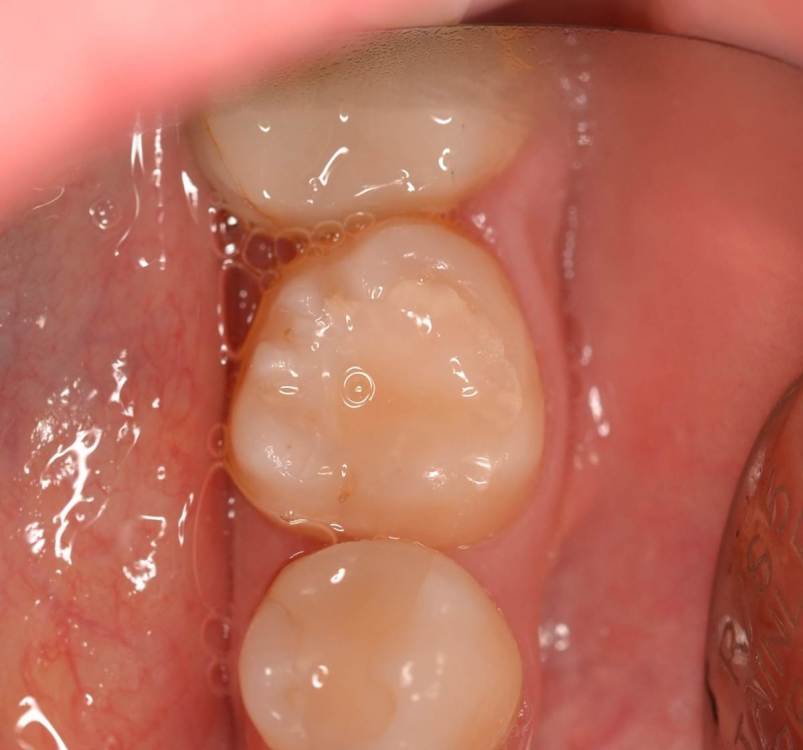

Dr.Deletle Опубликовано 22 июля, 2023 Поделиться Опубликовано 22 июля, 2023 (изменено) Этот кейс интересен тем, что у пересаживаемого 2.8 полностью сформированы корни. Пациент Н., 35лет, зуб 3.6 подлежит удалению по терапевтическим показаниям. Донором был выбран зуб 2.8. Фото №1, 2 - ситуация ДО на фото и срезе КЛКТ Фото №3 - планирование на реконструкции ОПТГ из КЛКТ Фото №4 - шаблон зуба 2.8 Фото №5, 6 - операция, удален 3.6, припасован шаблон, пересажен 2.8 (фиксирован швами и шиной к 3.7) Фото №7 - КТ сразу после пересадки Фото №8, 9 - депульпирование пересаженного 2.8 через 2 недели Фото №10 - снятие шины через 2нед после пересадки Фото № 11, 12, 13 - состояние в полости рта и на срезе КТ через год после пересадки, видно сформированное периодонтальное пространство, здоровая костная ткань, жалоб у пациента нет, полноценно жует как обычным зубом Изменено 22 июля, 2023 пользователем Dr.Deletle 4 3 Ссылка на комментарий